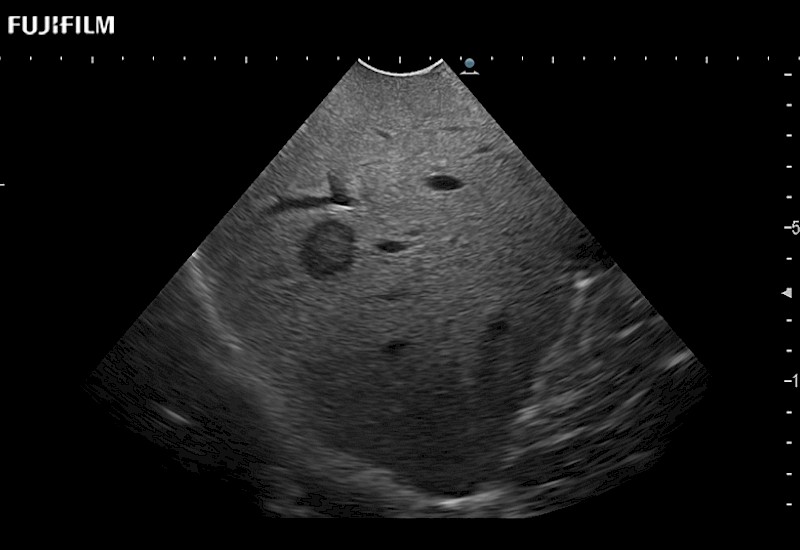

for use during general and laparoscopic procedures: Tumor localization & staging, Ablation, Resection, Biopsy, Transplant, Abdominal exploration, Robotic surgery

Our dedication to Laparoscopic Surgery allows us to offer superior image quality, outstanding system reliability and intuitive use of cutting edge technology.